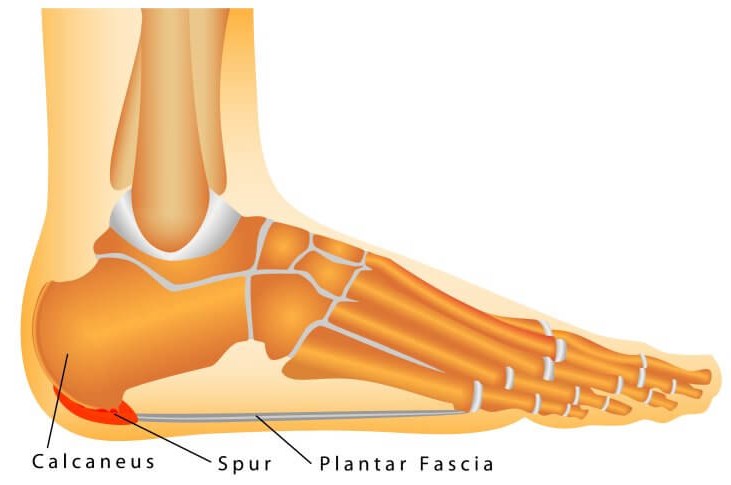

Pain in the foot and ankle joint is a fairly common problem that occurs in patients, especially those who are physically active. Ankle pain can be related to pain in the bone itself, pain in the tissues around the bone, such as the tendons of the fibular muscles, or it can be pain related to ligament damage, such as after an ankle sprain.